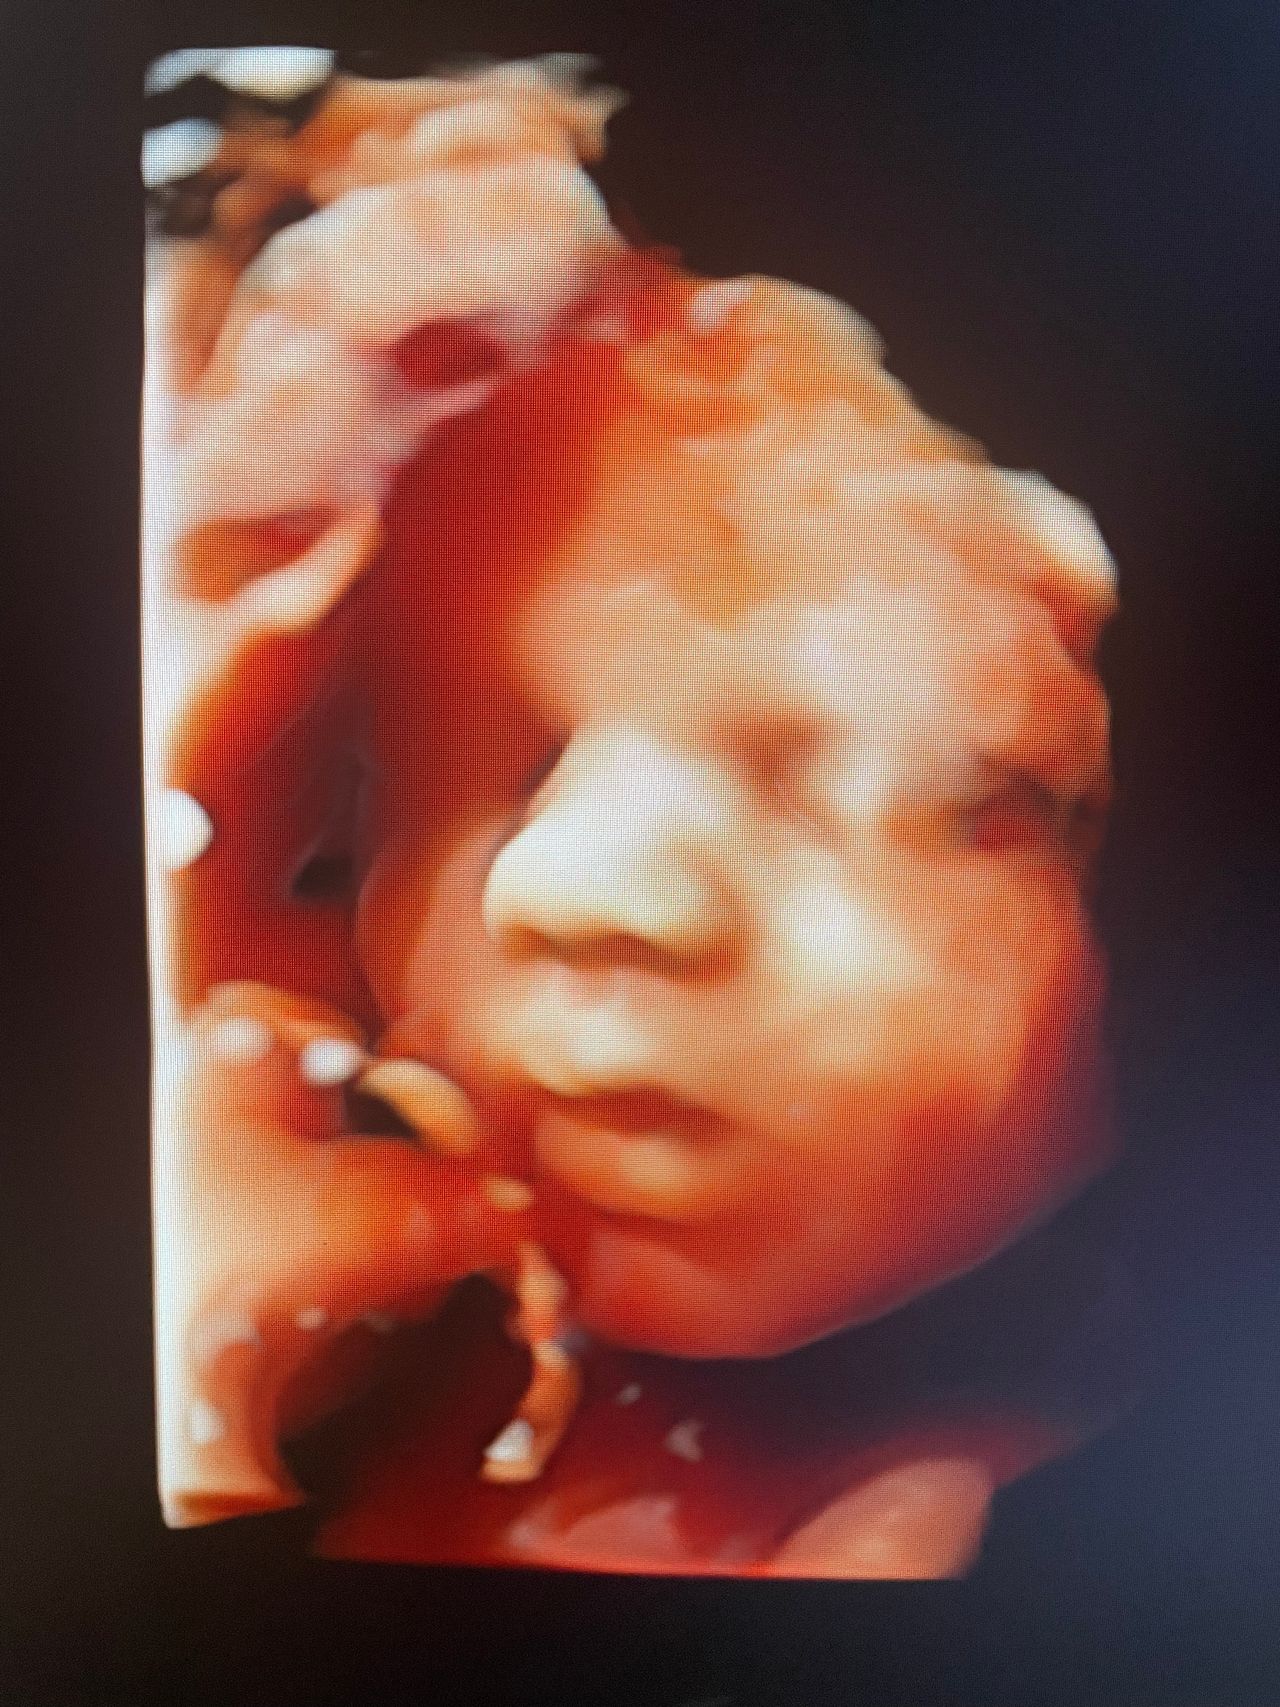

In gravidanza effettuo visite ostetriche, ecografie del I trimestre (datazione e translucenza nucale), calcolo del rischio del I trimestre (Bi test), cervicometria, ecografie del III trimestre (accrescimento e flussimetria fetale) ed ecografie 3D/4D.